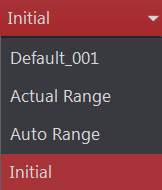

Preset window/level menu

Window/Level Predefined Settings

Predefined settings are available for the selected image in the Window/Level dropdown on the Window/Level toolbar.

Actual Range |

A full window width, centered in the middle of the maximum range, as defined by the encoded image information |

Auto Range |

The result of a histogram equalization analysis performed on the data. In most cases, this results in a smaller distribution than the actual range due to the interpretation of the pixel data values |

Initial |

default window width and center values explicitly defined in the image object |

Note: The Initial, Actual Range and Auto Range settings cannot be deleted or modified.